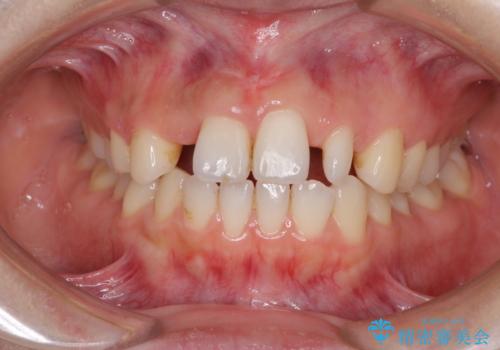

- 前歯の隙間を気にして来院された患者様です。

診察の結果、前歯が1本欠損しており、さらに矮小歯(通常よりも小さい歯)が1本存在していました。

欠損による前歯のスペースが大きかったため、事前にワイヤー矯正で前歯の位置を大きく動かし、その後は上下をインビザラインで整えることとしました。

矯正治療後には欠損部はオールセラミックブリッジに、矮小歯はオールセラミッククラウンにて補綴することとしました。